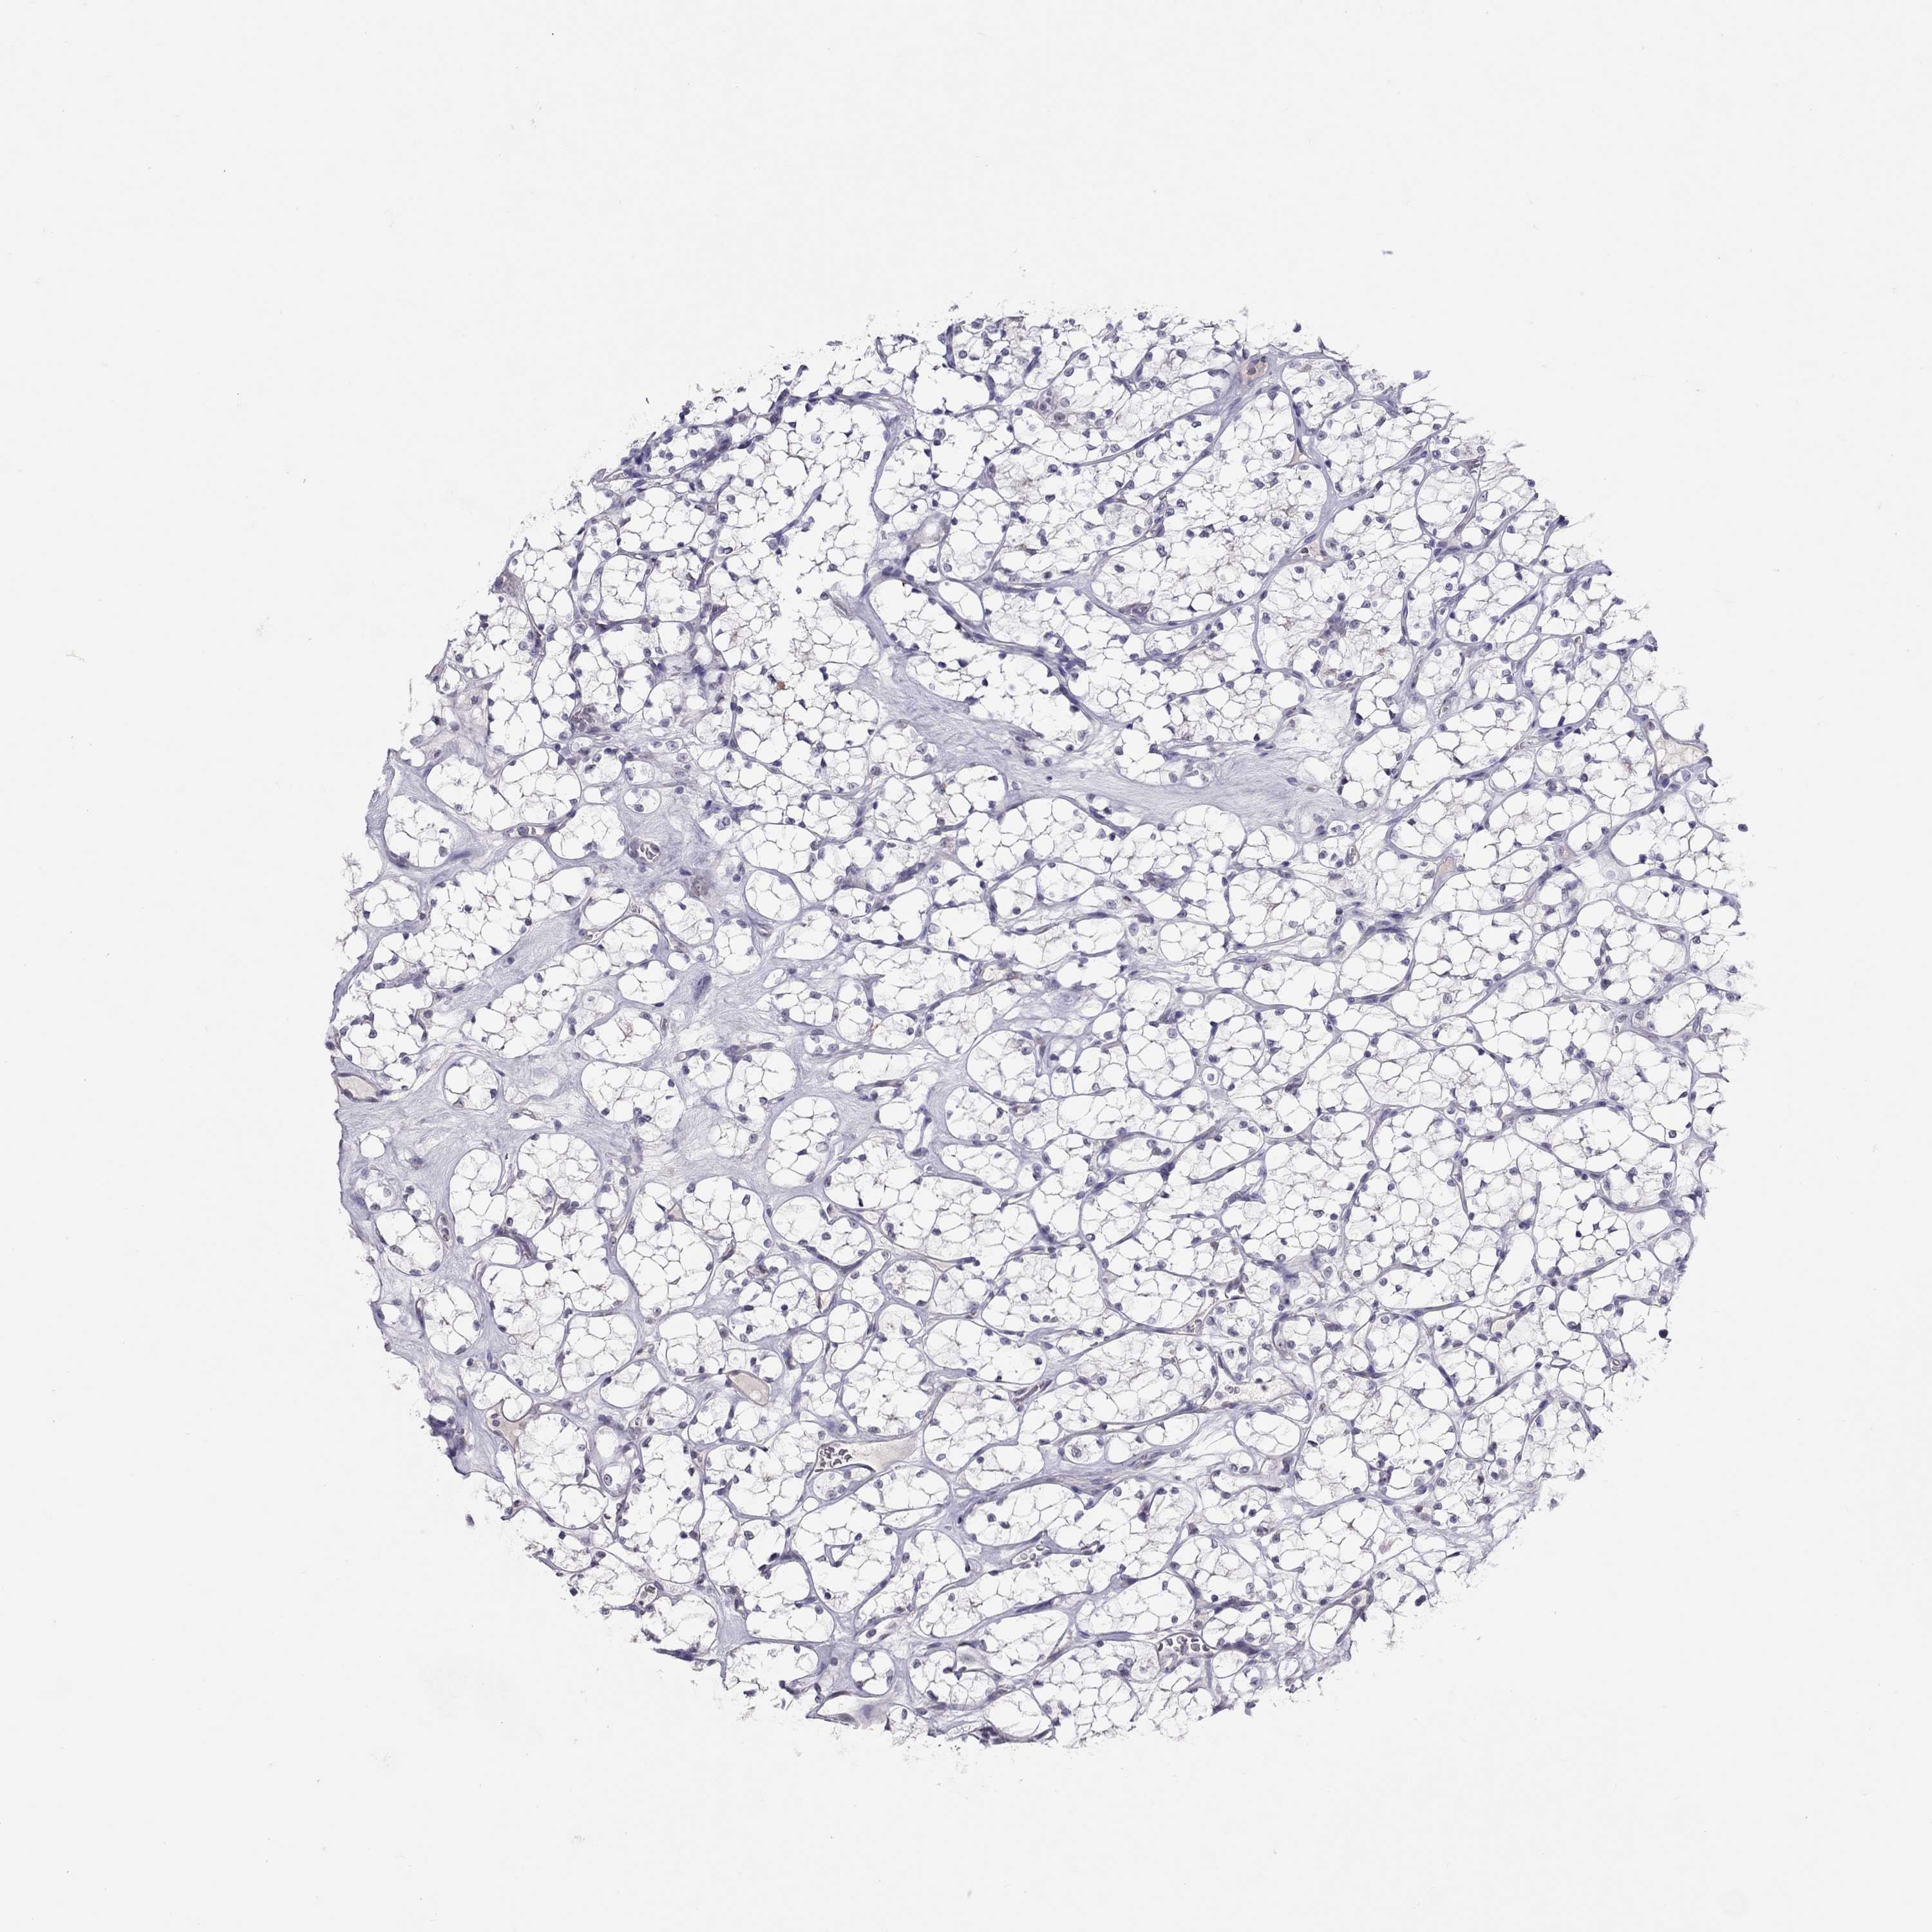

KIDNEY RENAL CLEAR CELL CARCINOMA (TCGA) - Interactive survival scatter ploti

The Survival Scatter plot shows the clinical status (i.e. dead or alive) for all individuals in the patient cohort, based on the same data that underlies the corresponding Kaplan-Meier plots. Patients that are alive at last time for follow-up are shown in blue and patients who have died during the study are shown in red.

The x-axis shows the expression levels (FPKM) of the investigated gene in the tumor tissue at the time of diagnosis. The y-axis shows the follow-up time after diagnosis (years). Both axes are complimented with kernel density curves demonstrating the data density over the axes. The top density plot shows the expression levels (FPKM) distribution among dead (red) and alive patients (blue). The right density plot shows the data density of the survived years of dead patients with high and low expression levels respectively, stratified using the cutoff indicated by the vertical dashed line through the Survival Scatter plot. This cutoff is automatically defined based on the FPKM cutoff that minimizes the p-score. The cutoff can be changed by dragging the vertical line or by entering a cutoff value in the square labeled "Current cut-off".

Under the Survival Scatter plot the p-score landscape (black curve; left axis) is shown together with dead median separation (red curve; right axis). Dead median separation is the difference in median mRNA expression between patients who have died with high and low expression, respectively. It is calculated as follows: median FPKM expression of dead patients with high expression - median FPKM expression of dead patients with low expression. This is intended to aid the user in visually exploring custom cutoffs and the associated p-scores and dead median separation.

Individual patient data is displayed and can be filtered by clicking on one or more of the category buttons on the top of the page. Categories describing expression level and patient information include: high, low, alive, dead, female, male and tumor stages. The scale of the x-axis can be toggled between linear and log-scale by clicking on the "x log" button. Mouse-over function shows TCGA ID, patient information and mRNA expression (FPKM) for each patient.

& Survival analysisi

Kaplan-Meier plots summarize results from analysis of correlation between mRNA expression level and patient survival. Patients were divided based on level of expression into one of the two groups "low" (under cut off) or "high" (over cut off). X-axis shows time for survival (years) and y-axis shows the probability of survival, where 1.0 corresponds to 100 percent.

JHY is potential prognostic, high expression is favorable in Kidney Renal Clear Cell Carcinoma (TCGA)

Best expression cut offi

Based on the FPKM value of each gene, patients were classified into two groups and association between prognosis (survival) and gene expression (FPKM) was examined. The best expression cut-off refers the FPKM value that yields maximal difference with regard to survival between the two groups at the lowest log-rank P-value. Best expression cut-off was selected based on survival analysis .

When clicking on this number, the vertical dashed line indicating cut-off, the interactive survival plot, and the Kaplan-Meier curve will be adjusted to show results based on the best expression cut-off.

: 2.89

Median expressioni

Median expression refers to the median FPKM value calculated based on the gene expression (FPKM) data from all patients in this dataset. When clicking on this number, the vertical dashed line indicating cut-off, the interactive survival plot, and the Kaplan-Meier curve will be adjusted to show results based on the median expression.

: N/A

Median follow up timei

Median follow up time refers to the median time (years) after diagnosis with this type of cancer, based on clinical data from all patients in this dataset.

P scorei

Log-rank P value for Kaplan-Meier plot showing results from analysis of correlation between mRNA expression level and patient survival.

N/A

5-year survival highi

5-year survival for patients with higher expression than the expression cutoff.

For melanoma and glioma, 3-year survival is shown.

5-year survival lowi

5-year survival for patients with lower expression than the expression cutoff.

TCGA RNA samplesi

RNA-seq data is reported as average FPKM (number Fragments Per Kilobase of exon per Million reads), generated by the The Cancer Genome Atlas (TCGA) .

Normal distribution across the dataset is visualized with box plots, shown as median and 25th and 75th percentiles. Points are displayed as outliers if they are above or below 1.5 times the interquartile range. FPKM values of the individual samples are presented next to the box plot.

Average pTPM 3.7

Number of samples 521